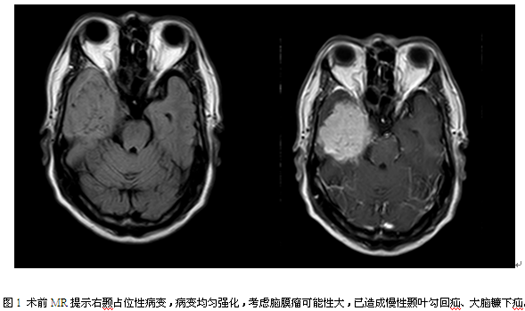

入院查体:神志清,对答切题,心胸腹查体未见明显异常,左侧肢体肌力4级,右侧肢体活动正常。查头颅MR右侧颞部示一团块状长T1稍长T2异常信号影,FLAIR序列呈稍高信号,其内示多发细小血管影,范围约69mm×58mm×53mm,增强后较均匀明显强化;部分边缘示小囊状明显长T1长T2异常信号影,FLAIR序列呈低信号,增强后未见强化;周围示环片状长T1长T2异常信号影,FLAIR序列呈高信号水肿影。双侧大脑半球皮层下白质内、双侧半卵圆中心及双侧侧脑室周围示散在点片状等或稍长T1长T2异常信号影,FLAIR序列呈高信号。右侧侧脑室受压变窄,左侧侧脑室轻度扩大,余脑室系统未见扩张,幕上脑沟轻度增宽,脑回稍变细,余脑沟、脑裂及脑池未见增宽,中线结构居中。于2016-04-11行右颞占位性病变切除术。